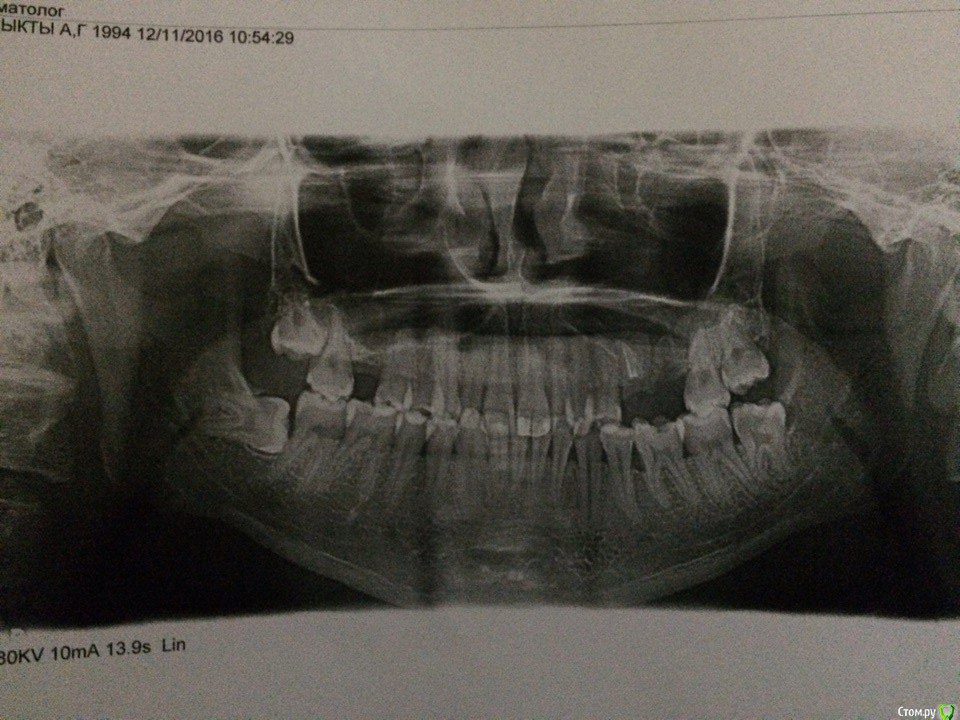

kyzykty1894 Опубликовано 30 ноября, 2016 Поделиться Опубликовано 30 ноября, 2016 Здравствуйте! У меня была перфорация гайморовой пазухи после удаления 6-го зуба (левая сторона), но, к счастью, я сразу же обратился в больницу Челюстно-Лицевую. И мне там сделали операцию, под местной. Почистили и зашили. Потом, через 1,5 недель удалили швы. Проблема такова, что когда разговариваю громко и дышу, у меня появляется острая боль, как будто типа удара воздуха, или как описать, давление на эту область, неприятная. Что мне дальше делать? завтра праздник у нас, и завтра я не могу обратиться к врачу, мне надо срочно же пойти к врачу, который делал операцию мне? или как? нужен от Вас хороший и грамотный совет. Спасибо заранее!!! Ссылка на комментарий

kyzykty1894 Опубликовано 29 декабря, 2016 Автор Поделиться Опубликовано 29 декабря, 2016 сколько времени прошло после операции? Сообщение с синусом устранено полностью? Какое либо консервативное лечение в настоящее время проводится (капли-спрей)?Здравствуйте, вот к сожаланию там есть свищевой вход, я второй раз его зашивал, но она открылась, терерь могу попасть после праздников. А этот свищевой вход не закроется сама? Ну вдруг мясо выростит, или я навиный человек Ссылка на комментарий